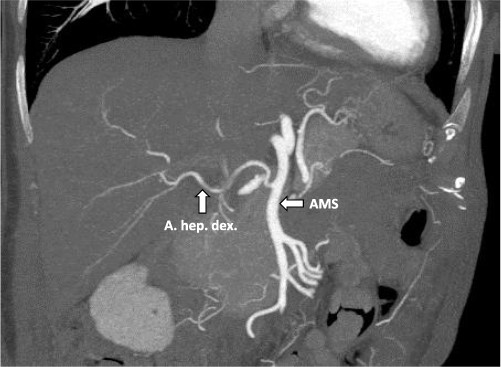

After multidisciplinary tumor board (MDT) discussion, neoadjuvant chemotherapy with six cycles of FOLFOXIRI and Bevacizumab followed by liver-first approach was decided. Restaging after 3 months showed stable disease of the CRLM, therefore, chemotherapy was continued. After 12 cycles, restaging revealed a size reduction of 12% of the CRLM (Fig. 1B). CEA decreased from 69 to 6.1 ug/l. The patient was then admitted to our department for the evaluation of a curative intent CRLM resection. The radiological work-up revealed three remaining metastases on the left- and seven on the right hemiliver. Volumetry illustrated a standardized FLR (sFLR) for a right hemihepatectomy of 30%. In an MDT and the patient was deemed amenable to ALPPS surgery due to the marginal sFLR, bilobar metastases and exceptionally good performance status. Preoperative liver function tests showed normal liver function (LiMAx 450 mcg/kg/h, cut-off >315 mcg/kg/h and ICG R15: 4.0%, cutoff <12%). Although liver biopsy is not routinely performed before ALPPS, MDT recommended a biopsy of the healthy liver to rule out chemotherapy-associated steatohepatitis after 12 cycles of FOLFOXIRI and Bevacizumab in order to ensure a safe liver resection. The biopsy showed signs of subacute hepatocyte demise without fibrosis or cirrhosis. The day after the liver biopsy, the patient collapsed and was admitted to the emergency department of another hospital. CT scan showed a large intrahepatic hematoma (Fig. 2) without active bleeding probably secondary to the biopsy procedure. Due to a hemoglobin drop of 12 g/l a day later and the enlargement of the hematoma in follow-up CT scan, the patient was admitted to angiography, which showed several subcapsular liver bleedings, therefore the right hepatic artery was embolized. Luckily, an accessory right hepatic artery arising from the superior mesenteric artery was present. This enabled us to stay on track with the ALPPS procedure as the right hemiliver would be otherwise without any blood supply (Fig. 3). In synopsis of those findings, the operation was scheduled.

CT-angiography showing the accessory right hepatic artery originating from the superior mesenteric artery.

Our presented case is the first to describe a successful ALPPS procedure after an emergency embolization of the right hepatic artery due to active bleeding thanks to the anatomical variation with an accessory right liver artery. In general, embolization of right hepatic artery is an absolute contraindication for right-sided ALPPS as ligating of the right portal vein would have left the right liver without any blood supply. Alternative options for this patient would have been a conventional two-staged hepatectomy after PVE or liver venous deprivation (LVD), as LVD induces a greater and faster liver hypertrophy than PVE. However, these methods were shown to be inferior to ALPPS in terms of liver hypertrophy rate and successful resection rates of CLRM [8]. Fortunately, in our case, arterial blood flow after ALPPS step 1 could be ensured through an accessory right liver artery, which was spared from the emergent embolization procedure. Therefore, ALPPS procedure could be performed as planned. A previous case report [9] described a patient with an aberrant right hepatic artery arising from the superior mesenteric artery (type III according to the Michel classification [10]), which was preserved during first stage of ALPPS. However, on the second postoperative day, the patient from the report by Sanjeevi et al. developed laboratory signs of an acute liver failure due to occlusion of right hepatic artery. Nevertheless, the FLR increased from 290 to 746 ml within 6 days. Despite the occluded right artery, the patient underwent stage 2 on the seventh postoperative day and had an unremarkable further recovery [9]. In previous unhealthy livers, the increase of the FLR may be limited due to severe fibrosis or cirrhosis. In patients who failed to achieve adequate FLR growth after stage 1, Peng et al. described an ALPPS modification in which the arterial supply of HCC was occluded using transarterial embolization (TAE) 14 days after ALPPS stage 1, followed by ALPPS stage 2 7 days later [11]. In this relation, TAE-associated complications were grade A posthepatectomy liver failure, tumor lysis syndrome and ascites resulting in a TAE-specific morbidity rate of 20%. Nonetheless, TAE resulted in significant increases of FLR, kinetic growth rates from 8.9 to 19.5 ml/day after TAE, showing a promising modification of ALPPS in HCC.

For successful ALPPS, adequate arterial blood supply to the resected hemiliver needs to be preoperatively ensured. Luckily, the anatomy of an accessory right hepatic artery allowed us to perform ALPPS after emergency embolization of the right hepatic artery. In addition, the case exemplifies that preoperative evaluation of the vascular supply of the liver is of paramount importance in advanced hepatic surgery such as ALPPS.